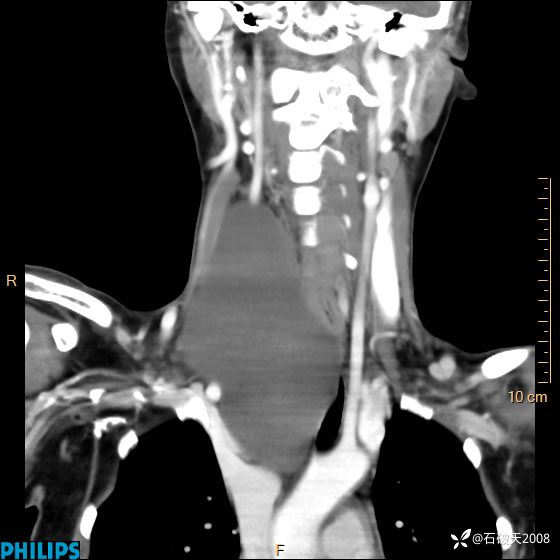

冠状位

静脉期